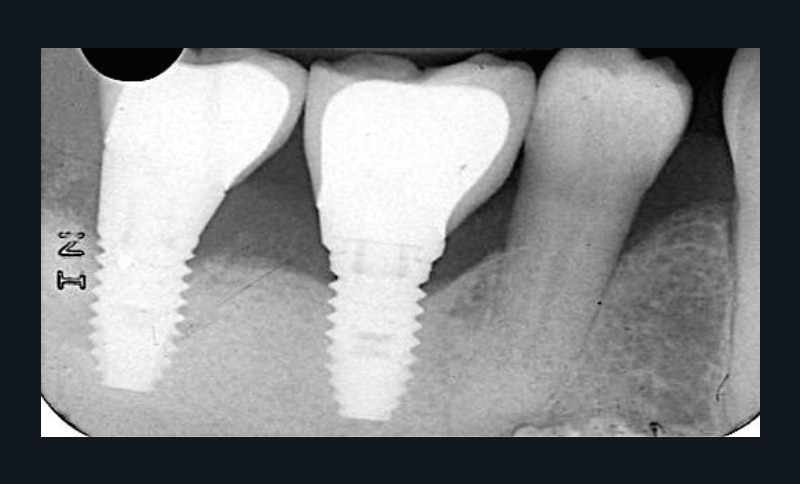

La mucosite

La mucosite, stade précédant la péri-implantite, se caractérise par un syndrome inflammatoire autour des implants avec des valeurs de sondage variables sans perte osseuse (fig. 2).